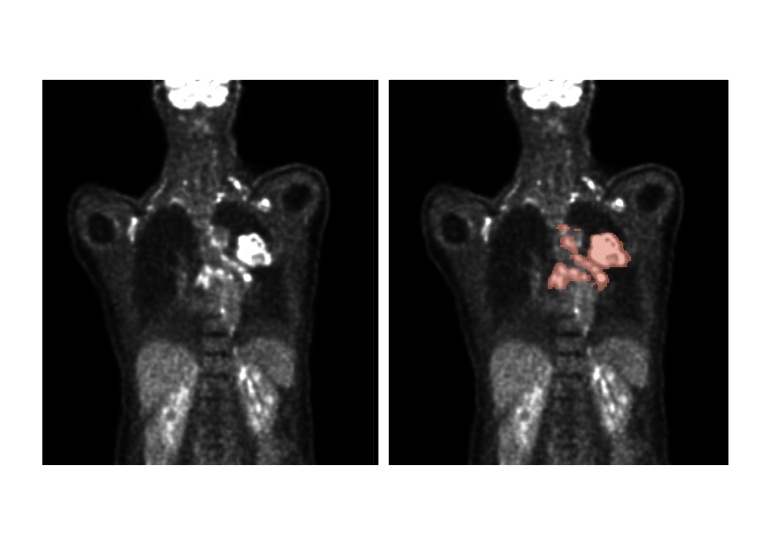

Künstliche Intelligenz kann die Auswertung von medizinischen Bilddaten verbessern. So können auf Deep Learning basierende Algorithmen die Lage und Größe von Tumoren feststellen.

Bei der Diagnose von Krebs kommt bildgebenden Verfahren eine wesentliche Bedeutung zu. Die Lage, Größe und Art von Tumoren präzise zu bestimmen, ist entscheidend dafür, die passende Therapie zu finden. Zu den wichtigsten bildgebenden Verfahren gehören die PET und die CT. Die PET macht Stoffwechselvorgänge im Körper mithilfe von Radionukliden sichtbar. Bösartige Tumoren haben oft einen deutlich intensiveren Stoffwechsel als gutartige Gewebe. Verwendet wird dazu radioaktiv markierter Traubenzucker, meist Fluor-18-Desoxyglucose (FDG). Bei der CT wird der Körper in einer Röntgenröhre Schicht für Schicht durchleuchtet, um die Anatomie sichtbar zu machen und Tumoren zu lokalisieren.

Rainer Stiefelhagen und Zdravko Marinov, Doktorand am cv:hci, haben 2022 am internationalen Wettbewerb autoPET teilgenommen und unter 27 Teams mit 359 Teilnehmenden aus aller Welt den fünften Platz erreicht. Dabei bildeten die Karlsruher Forscher mit Professor Jens Kleesiek und Lars Heiliger vom IKIM – Institut für Künstliche Intelligenz in der Medizin in Essen ein Team. Organisiert vom Universitätsklinikum Tübingen und vom LMU Klinikum München, verband autoPET Bildgebung und maschinelles Lernen. Die Aufgabe bestand in der automatischen Segmentierung stoffwechselaktiver Tumorläsionen auf Ganzkörper-PET/CT. Für das Algorithmentraining hatten die teilnehmenden Teams Zugang zu einem großen kommentierten PET/CT-Datensatz. Alle für die letzte Phase des Wettbewerbs eingereichten Algorithmen basieren auf Methoden des Deep Learning. Dabei handelt es sich um einen Bereich des maschinellen Lernens, der vielschichtige künstliche neuronale Netze einsetzt, um komplexe Muster und Zusammenhänge in großen Datenmengen zu erkennen. Die sieben besten Teams aus dem Wettbewerb autoPET berichteten dies in der Zeitschrift Nature Machine Intelligence über die Möglichkeiten automatisierter Auswertung medizinischer Bilddaten.

Wie die Forschenden in ihrer Publikation erklären, erwies sich ein Ensemble der bestbewerteten Algorithmen als überlegen gegenüber einzelnen Algorithmen. Das Algorithmenensemble kann die Tumorläsionen effizient und präzise erkennen. „Die Leistung der Algorithmen bei der Bilddatenauswertung hängt allerdings von der Quantität und der Qualität der Daten ab, aber auch vom Algorithmendesign, beispielsweise was die Entscheidungen bei der Nachbearbeitung der vorhergesagten Segmentierung betrifft“, erklärt Professor Rainer Stiefelhagen. Um die Algorithmen zu verbessern und robuster gegenüber äußeren Einflüssen zu machen, sodass sie sich im klinischen Alltag einsetzen lassen, sind weitere Forschungsarbeiten erforderlich. Ziel ist, die Analyse der medizinischen Bilddaten aus PET und CT in näherer Zukunft vollständig zu automatisieren.